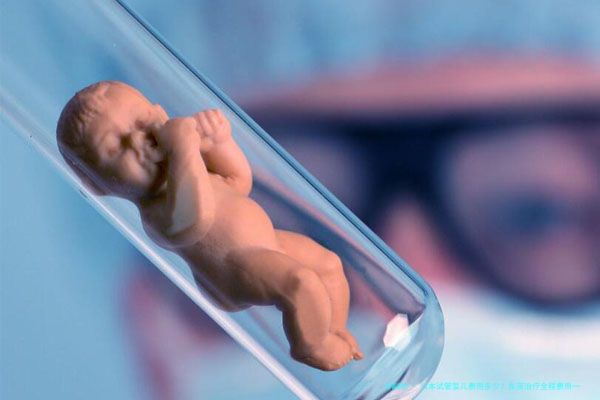

在当今社会,随着科技的发展,试管婴儿技术已然成为了很多不孕不育家庭解决生育问题的希望。日本作为试管婴儿技术的先驱其中一个,其先进的医学技术和完整的医护服务招引了许多国际病患。如此,在日本进行试管婴儿手术,全程的费用到底是多少呢?本文将为您揭秘日本试管婴儿的费用一览。

⑷总结 在日本进行试管婴儿手术,全阶段费用大约在650,000至1,150,000日元之间。尽管费用相对较高,但日本在试管婴儿技术方面的先进特性和成功率较高,为众多不孕不育家庭带来了期望。如果您思量在日本进行试管婴儿治疗,建议早做好充沛的了解和筹备,为了便于更优地应对治疗过程中的各种费用问题。